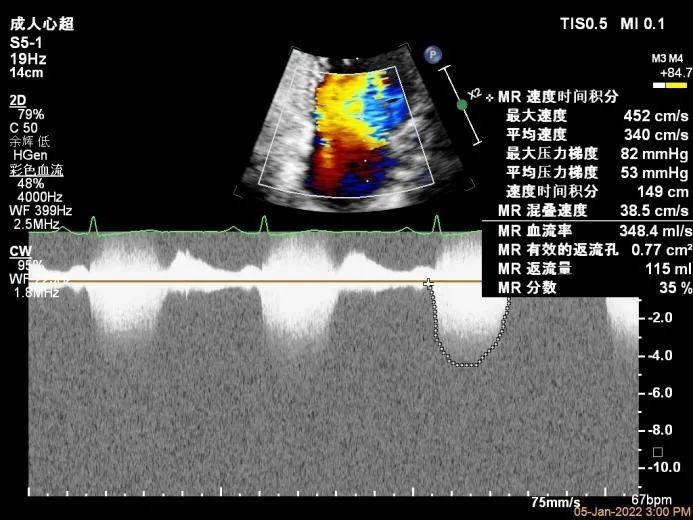

Bicom:MR(重度),返流束宽12mm,返流面积10.3cm2,PISA法定量EROA:

0.77cm2,Rvol:115ml,RF:35%,r:12mm。